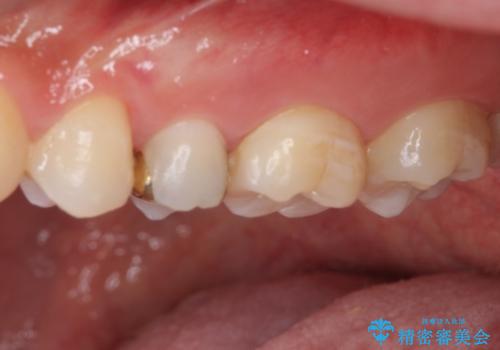

仮詰め材を外すと虫歯が残っていたので、全てを取り除いた後に、ゴールドインレーの型どりを行いました。

ゴールドインレーをご自身で選択いただいたものの、どういった仕上がりとなるか不安を感じていたようですが、実際に装着された口腔内をご覧になり、思ったほど金属色が気にならないとのことでした。

咬んだ感触はご自分の歯のときと比べ全く遜色なく、患者様には大変満足していただきました。